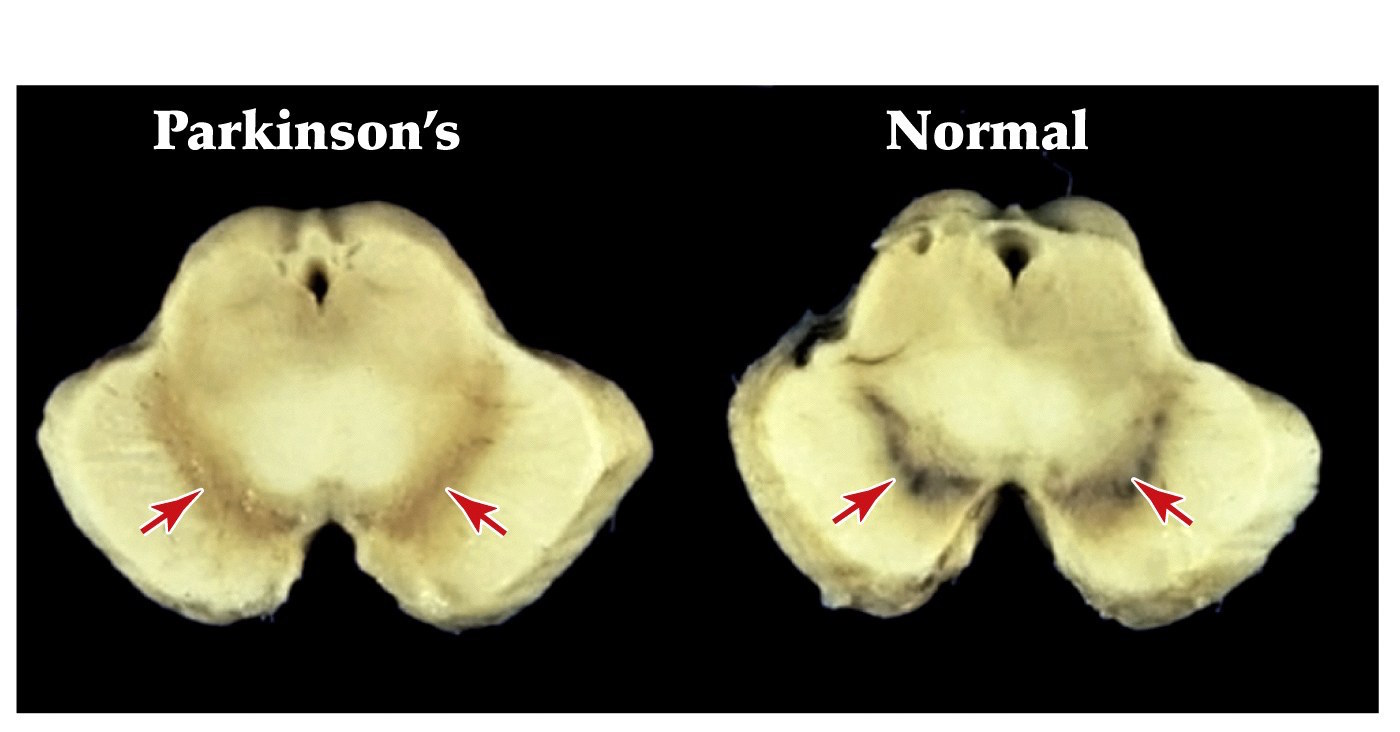

Parkinson’s disease

- Due to the degeneration of dopaminergic neurons of the substantia nigra pars compacta

- Leads to tremors, slowness of movements, rigidity of extremities and neck, minimal facial expressions

- Slowly progressing disease

- Some success in slowing the progression comes from the use of Levadopa (L-DOPA)– gets converted to dopamine and gets to dopamine receptors in basal ganglia

from https://en.wikipedia.org/wiki/Substantia_nigra

Substantia nigra is Latin for "black substance", reflecting the fact that parts of the substantia nigra appear darker than neighboring areas due to high levels of neuromelanin in dopaminergic neurons.

Parkinson’s disease

Pathophysiology is the loss of nigrostriatal dopaminergic projections from SNc

Parkinson’s- loss of dopamine making neurons in the midbrain's substantia nigra

Note:

substantia nigra pars compacta, a nucleus containing neurons making the neurotransmitter dopamine that are important for regulating motor movements via their connections with the basal ganglia and which are devastated in parkinson’s disease.

dark appearance due to high levels of dark pigment neuromelanin in dopaminergic neurons

Neuromelanin is directly biosynthesized from L-DOPA, precursor to dopamine, by tyrosine hydroxylase (TH)